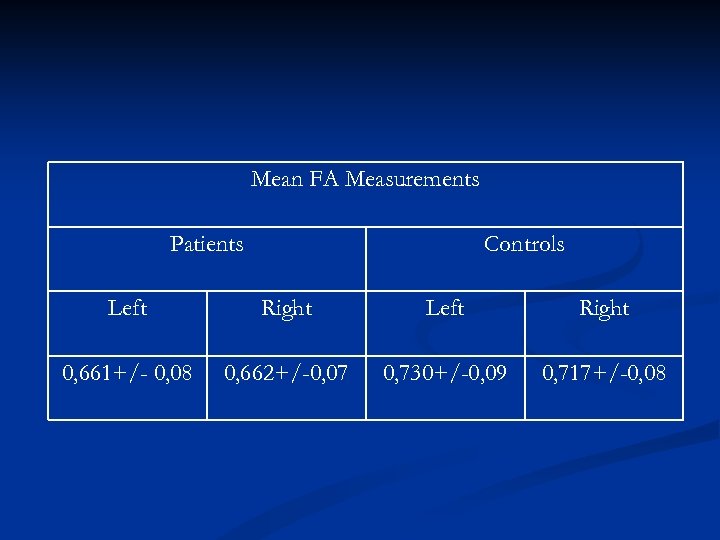

Comparing (FA) measurements, between controls and patients we found that FA measurements in patients were lower than in the age matched healthy subjects. A further decrease in FA measurements was also noticed with disease progression on the F/U study. Using fiber tractography we visualized the CST tract in healthy volunteers as well as ALS patients. A small number of patients, especially those with definite ALS, showed a visibly decreased volume of CST fibre bundles

Comparing (FA) measurements, between controls and patients we found that FA measurements in patients were lower than in the age matched healthy subjects. A further decrease in FA measurements was also noticed with disease progression on the F/U study. Using fiber tractography we visualized the CST tract in healthy volunteers as well as ALS patients. A small number of patients, especially those with definite ALS, showed a visibly decreased volume of CST fibre bundles

Mean FA Measurements Patients Controls Left Right 0, 661+/- 0, 08 0, 662+/-0, 07 0, 730+/-0, 09 0, 717+/-0, 08

Mean FA Measurements Patients Controls Left Right 0, 661+/- 0, 08 0, 662+/-0, 07 0, 730+/-0, 09 0, 717+/-0, 08